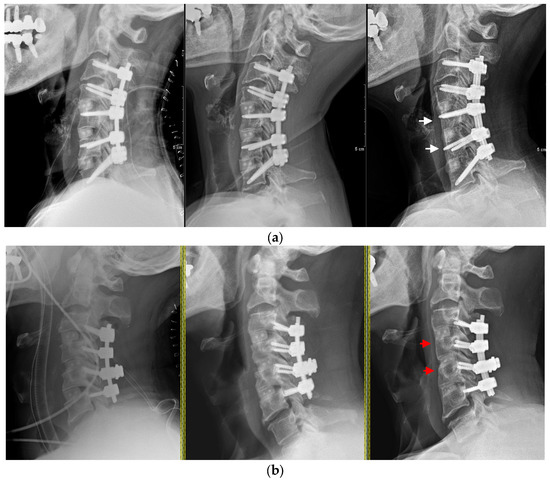

2. Materials and Methods

3.3. Subsidence

3.4. Vertebral Body Width